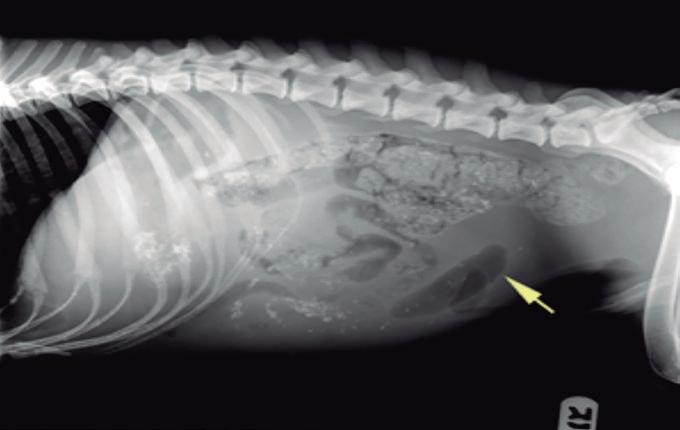

La radiología intervencionista es una especialidad que se encarga del diagnóstico y tratamiento de una gran cantidad de patologías de una forma mínimamente invasiva. Para realizar estos procedimientos es imprescindible disponer del equipamiento adecuado, tener nociones tanto de la instrumentalización como de las diferentes técnicas, y conocer con precisión la anatomía del paciente. Se trata de técnicas cada vez más implementadas en la clínica diaria ya que permiten solucionar diferentes patologías con una menor agresión a nivel tisular, una rápida recuperación, son procedimientos sin dolor, rápidos y seguros, suponen un menor coste respecto a otras cirugías invasivas, y constituyen una alternativa terapéutica a pacientes que no se pueden operar de forma convencional. Entre las más frecuentes destaca el cierre del conducto arterioso persistente, valvuloplastias en estenosis pulmonar, oclusión de shunts portosistémicos, implantación de marcapasos y colocación de stents

La radiología intervencionista se realiza mediante un abordaje guiado por distintas técnicas de imagen como, por ejemplo, la ecografía, la fluoroscopia o la tomografía computarizada, para alcanzar la zona a diagnosticar o tratar.

La radiología intervencionista, también conocida como radiología vascular e intervencionista, es una especialidad que se encarga del diagnóstico y tratamiento de una gran cantidad de enfermedades de una manera mínimamente invasiva. Se realiza mediante un abordaje guiado por distintas técnicas de imagen como, por ejemplo, la ecografía, la fluoroscopia o la tomografía computarizada, para alcanzar la zona a diagnosticar o tratar.

La radiología vascular e intervencionista ofrece una alternativa segura y eficaz a la cirugía en muchas enfermedades. Entre sus ventajas para el paciente destaca una menor agresión a nivel tisular, una rápida recuperación, procedimientos sin dolor, rápidos y seguros, un menor coste respecto a otras muchas cirugías con mis-